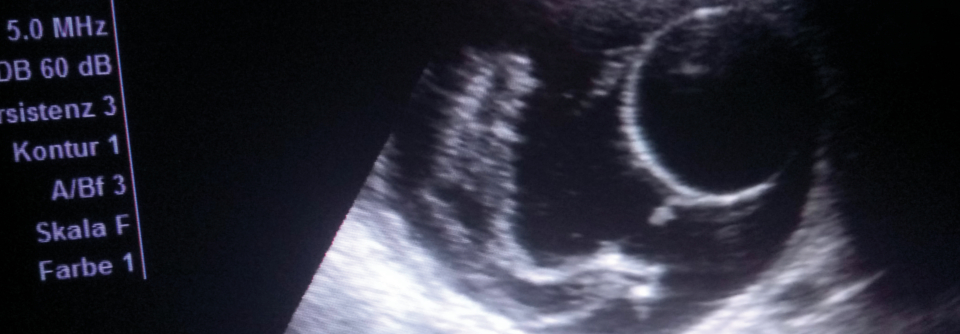

Auch in Deutschland muss man mit einer Bilharziose rechnen, wie das Beispiel eines 29-jährigen Patienten demonstriert. Der junge Mann konsultierte die Kelkheimer Dermatologin und Venerologin Dr. Hildegard­ Bonczkowitz­ wegen juckender progredienter Hautveränderungen an linker Leiste und Peniswurzel. Diese vermutete zunächst ein atypisches Lymphogranuloma venereum. Zwecks genauerer Abklärung entschloss sie sich zu einer Probeexzision. Die Histologen bestätigten den Infektionsverdacht der Venerologin. Statt der vermuteten Chlamydien fanden sie aber Schistosomen